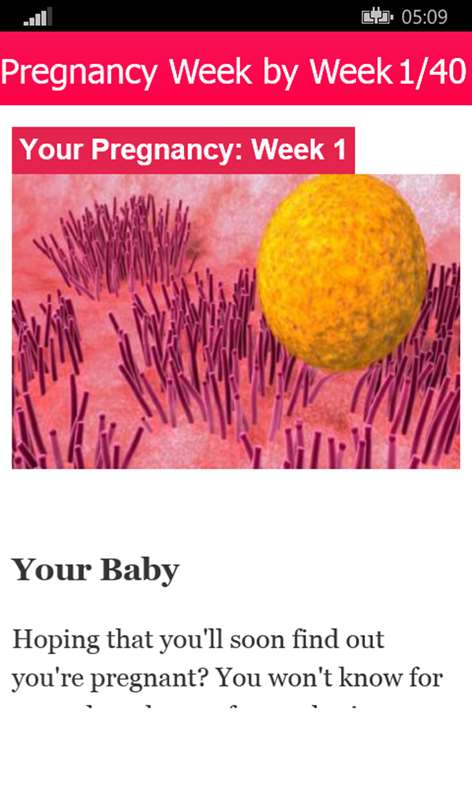

Pregnancy Week by Week

Follow your pregnancy week by week and get answers to your questions, like, "When will I show?" and "Is it too early to feel baby's kicks?"